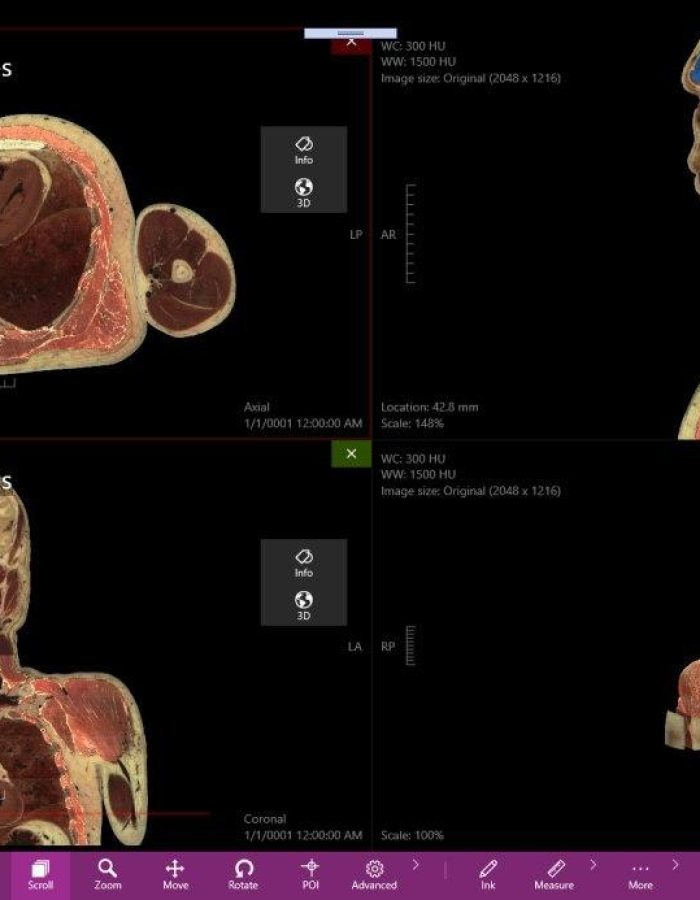

_ Amplia variedad de imágenes con un estilo profesional, tanto para estudios de casos pre operatorios como para estudio profundo de medicina.